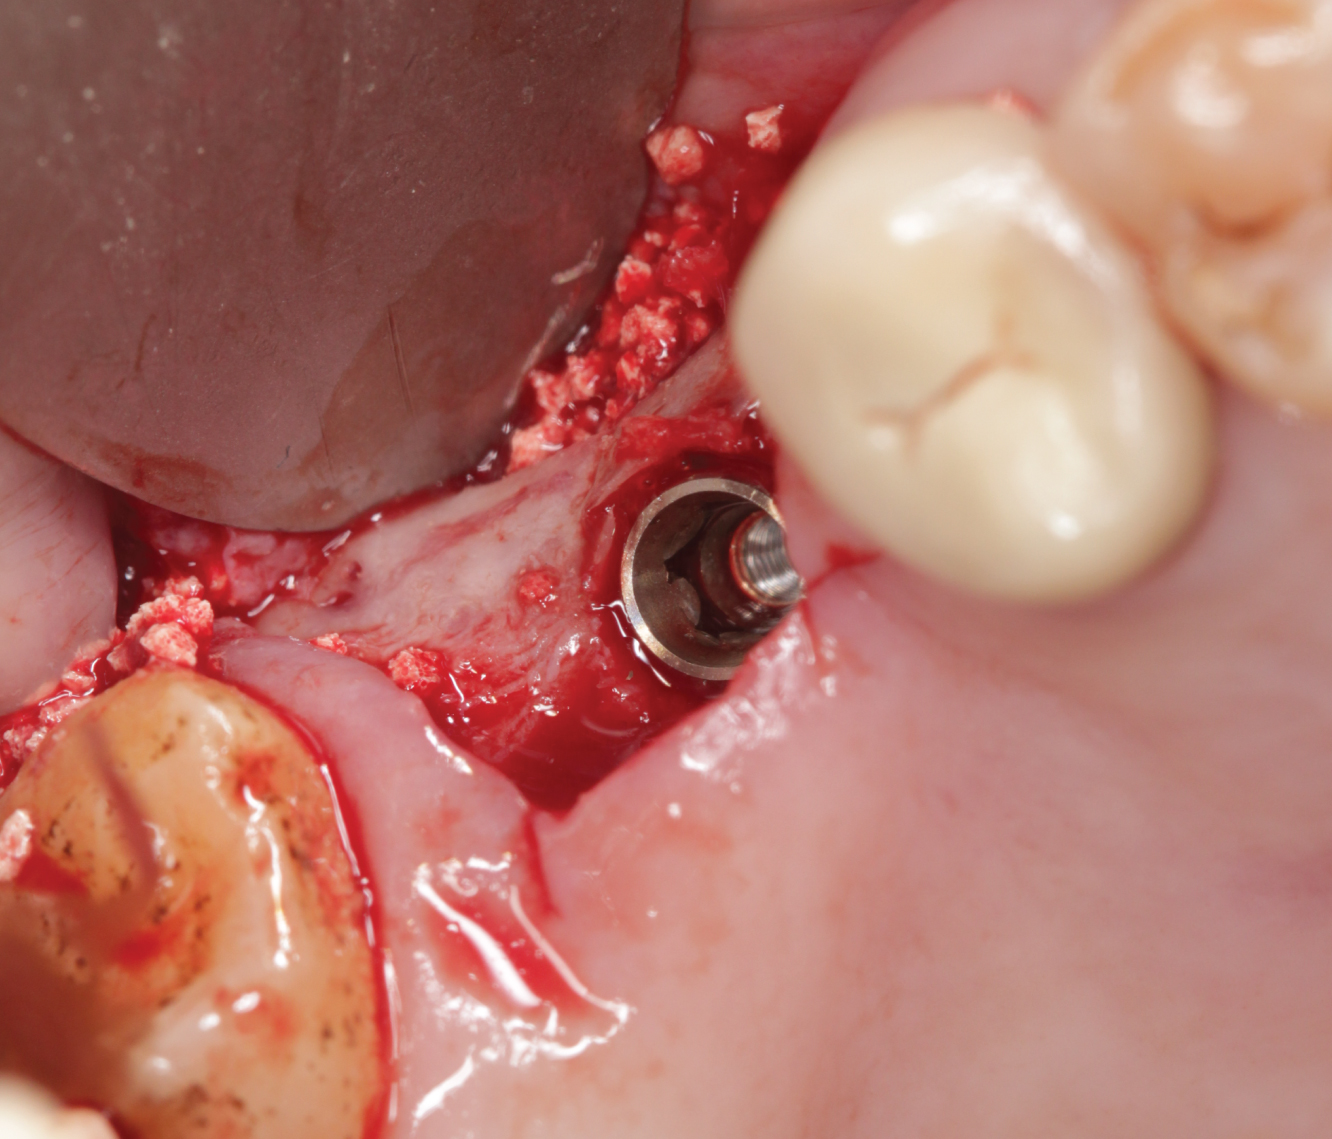

Director’s Clinical Cases

Director’s Clinical Cases